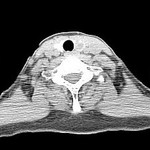

[画像診断]Wegener肉芽腫症の胸部CT所見について 2010-09-11